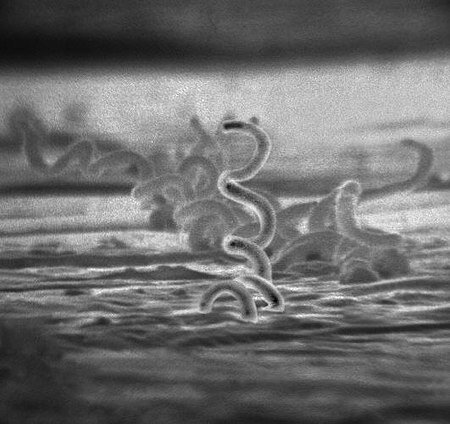

Бледная спирохета, возбудитель Сифилиса